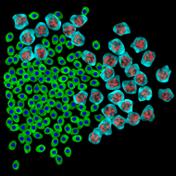

appropriate simulation algorithm. Figure 2 shows some examples of the obtained

Figure 2. Simulated synthetic images

images.similarity of experimental and generated synthetic images is not enough

real experimental images. That is why numerical comparison of the available

experimental images of cancer tumors and reproduced synthetic images was drawn.

The analysis of the intensity histograms of the affected

cells nuclei on simulated and experimental images in three colour channels was

conducted. The results showed similarity of the images intensity. The χ2 goodness of fit was used

to verify the quality of modelling and showed that the values did not exceed

critical values of χ2 at a significance level of 0.95

indicating that the statistical conditions of χ2 were satisfied., the

equivalent radii of nuclei on the experimental image were compared with those

on the simulated synthetic image. The χ2 goodness of fit was used

again for the objects distribution histogram according to the value of their

equivalent radii to check their conformity with the laws of distribution. The

calculation of χ2 values for 19 degrees of freedom

gave 9.61 which was less than the critical value of χ2 equal to 10.1 at a

significance level of 0.95.the process of cancer tumor cells modelling several